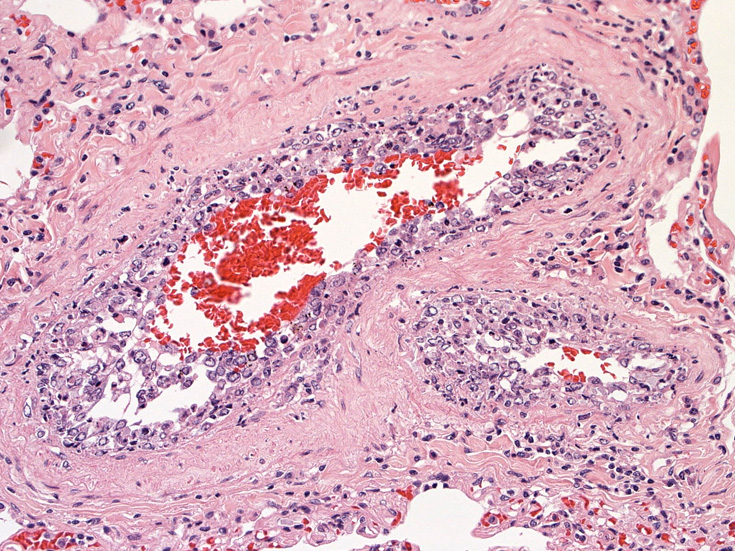

脳;くも膜下腔の小動脈内, 脳白質の細血管内に腫瘍細胞が充満している。

肺B;小気管支動脈, 肺動脈内を腫瘍細胞が閉塞する. 動脈内膜に浸潤性増殖している(B)。